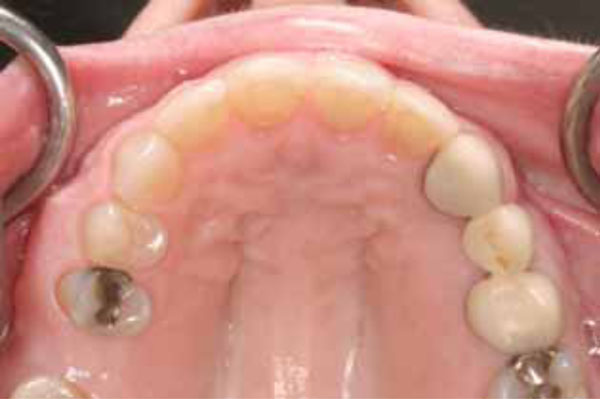

Upper arch after orthodontia.

The goal of orthodontic treatment was to return her teeth to their original pre-trauma positions. No effort was made to correct her Class II malocclusion, which was recognized and discussed but deemed unimportant by the patient. She had always been Class II, she was used to it, and it had not been a problem for her. Therefore, she did not wish to undertake any correction of that condition, and we were able to accommodate her preference in good faith. NiTi round wire (.012-inch) followed by NiTi heat-activated wire (.018 × .025-inch) in fixed metal (.022-inch) brackets was used to reposition the incisors (Figs. 11 and 12). The arch form was restored to a close approximation of the form that it had enjoyed prior to the incident. This correction enabled the patient to resume normal function by eliminating the protrusive interference and the lip biting problem. Examination of post treatment study casts shows overjet restored to original condition (Fig. 13). The comfort and restoration of normal function finally enabled the patient to smile again (Fig. 14).